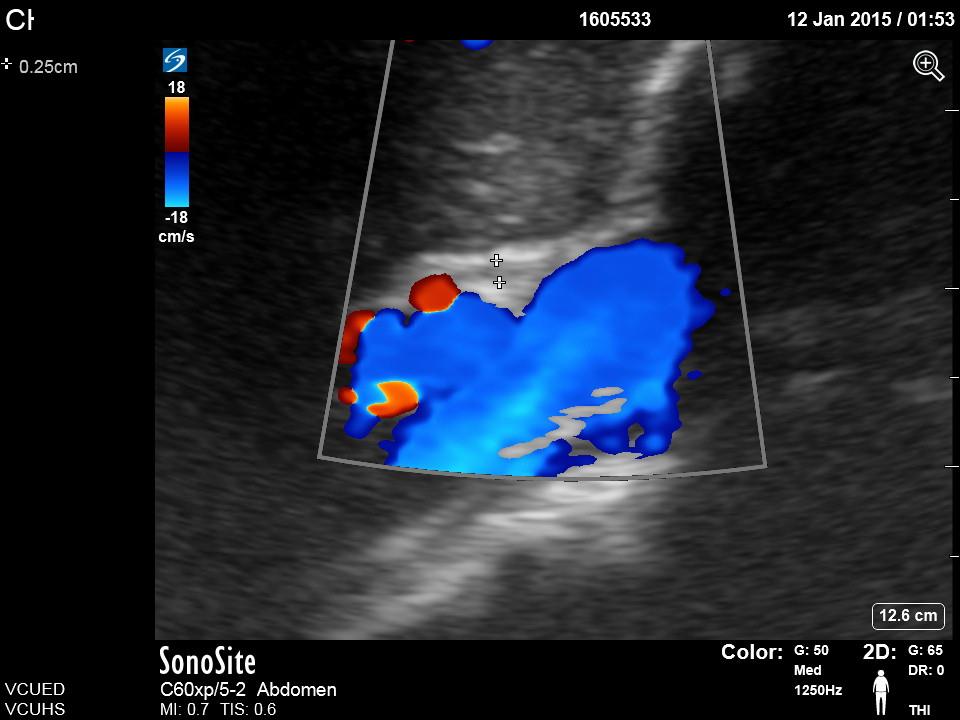

Biliary A. Clip of long axis of GB with portal triad https://vcuultrasound.com/wp-content/uploads/2020/07/0a613-video-8.1-gb-long-axis.mp4 B. Clip of scan through short axis of GB https://vcuultrasound.com/wp-content/uploads/2020/07/c6f26-video-8.2-gb-short-axis.mp4 C. Measurement of CBD with color flow (inner to inner wall) D. Measurement of GB wall in cross section at anterior portion from outer to inner Share this: Share on X (Opens in new window) X Share on Facebook (Opens in new window) Facebook Like Loading...